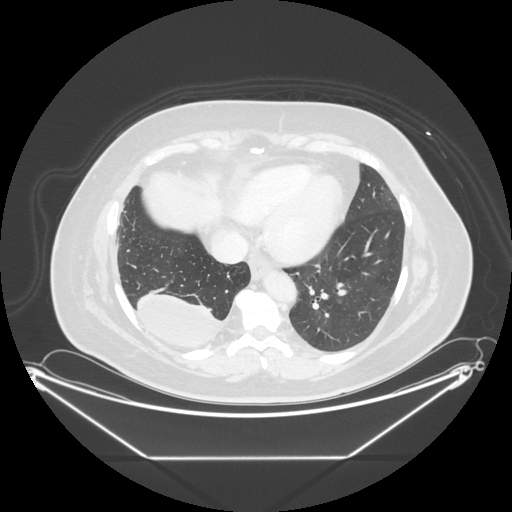

Original VENOUS CT scan

No window - Raw intensity values

Lung window (WL -600, WW 1500 β†’ Low βˆ’1350, High +150)

Mediastinum window (WL 40, WW 400 β†’ Low βˆ’160, High +240)